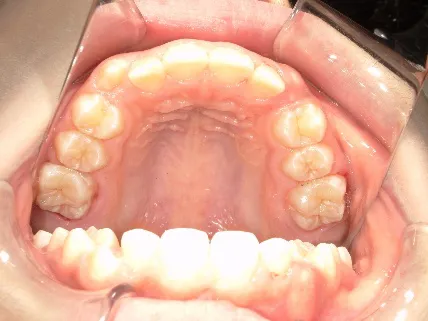

治療中③中1:非抜歯治療の診断で、上顎に歯の生えるスペースをつくるため上顎左右6をプレートで遠心移動し、隙間ができた時点

マルチブラケット法へ移行します

| 行ったご提案・診断内容 | 生え変わりが終わってなくマルチブラケット法による咬合治療には早い時期のため、顔立ちの成長を促す目的で歯列弓(アーチ)の拡大と前歯を並べながら永久歯が生えるのを待ち、咬合治療開始時に再診断で抜歯、非抜歯を最終検討する提案をしました。 再診断時(写真②)、歯列の拡大と上顎前歯の並べ替えはされていましたが八重歯となったため抜歯、非抜歯を検討しました。 口元は特に問題がなく非抜歯で八重歯を改善するためのスペースを作ることが可能なため非抜歯治療を提案しました。 治療は、 ・拡大および上顎左右6を遠心移動させてスペースを作る 予定装置 |